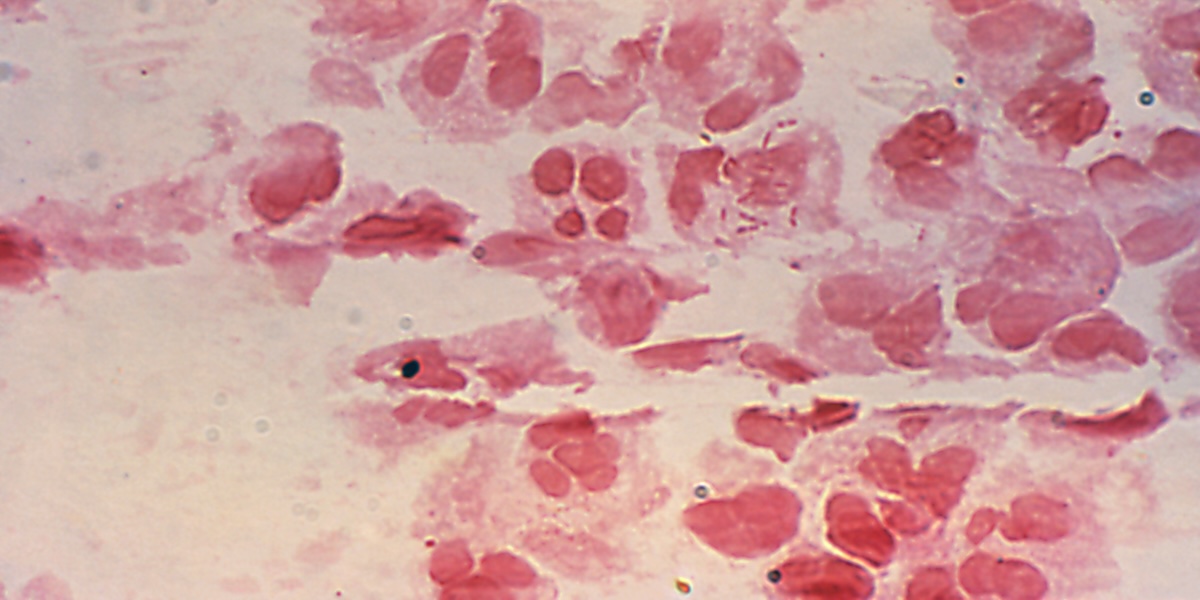

Una persona “tetracromatica” vede colori e tonalità che la maggior parte delle persone non riesce a vedere e di conseguenza nemmeno a concepire. Questa condizione è studiata da tempo ed è nota nel regno animale, ma i ricercatori finora non sono riusciti a capire moltissimo come funziona. Si sa che i “tetracromatici” riescono a vedere fino a 100 milioni di colori diversi, cioè quasi 100 volte la normale capacità di un essere umano di percepire i colori che ha intorno. La maggior parte delle persone ha tre tipi diversi di recettori sulla retina, che si occupano della visione del colore, mentre una persona “tetracromatica” ne possiede quattro, da cui deriva la capacità di vedere la luce in lunghezze d’onda di solito precluse all’occhio di una persona con la vista ordinaria.